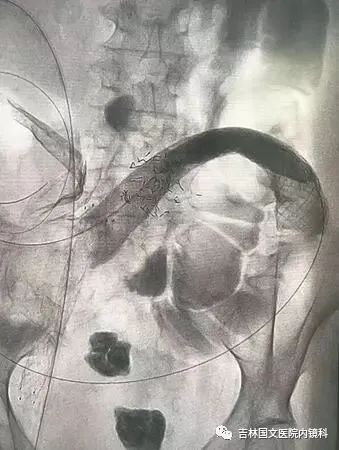

患者為結(jié)腸腫瘤致腸梗阻的病人,通過放置支架解除患者痛苦。手術(shù)開始,先置入導(dǎo)絲與導(dǎo)管,注入造影劑,顯示腸管走形,以確定狹窄段長度及部位,見乙狀結(jié)腸狹窄,造影劑可通過,但導(dǎo)絲至結(jié)腸狹窄處通過失敗,候主任決定聯(lián)合內(nèi)鏡,進(jìn)行多學(xué)科合作。

邢主任迅速到達(dá),循腔進(jìn)鏡至乙狀結(jié)腸腫瘤處,見腫瘤環(huán)形生長,腫瘤似豆腐渣樣脆弱又霸道的侵占著本來就不寬敞的路,中指一樣粗細(xì)的腸鏡是無法通過了,只能做一盞指路的明燈,帶領(lǐng)導(dǎo)絲駛?cè)肽康牡?,在邢主任富有?jīng)驗(yàn)的操作以及候主任隨機(jī)應(yīng)變地配合下,整個(gè)操作行云流水,導(dǎo)絲終于順利通過,送檢病理后,退出腸鏡。

又經(jīng)過一系列操作,腸道支架順利置入,患者術(shù)后排出大量稀便及氣體,腹脹明顯緩解,解決了患者的生理難題,提高了生活質(zhì)量。